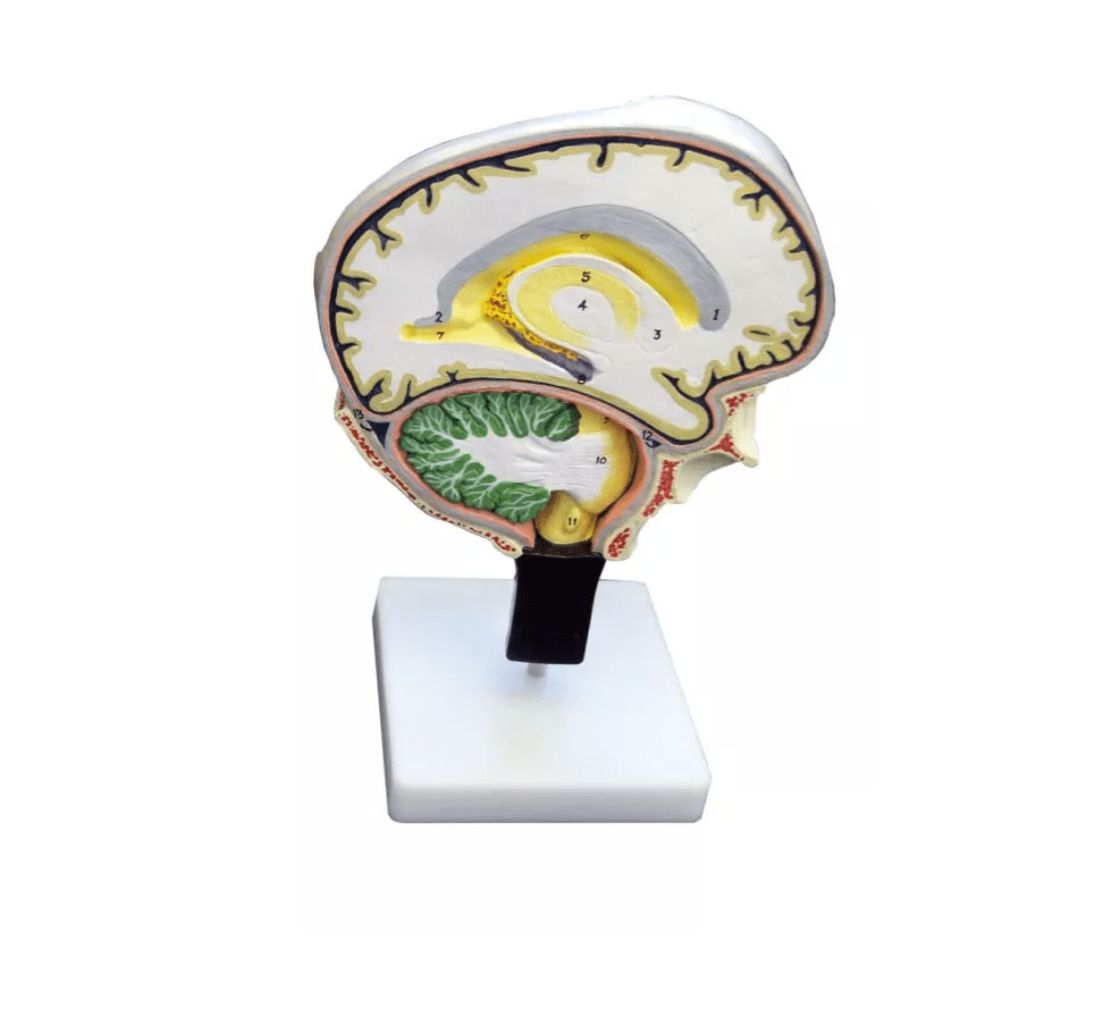

Dieses besonders detaillierte und vergrößerte Modell zeigt einen anatomisch präzisen Schnitt durch die rechte Gehirnhälfte, ergänzt um einen Teil des Schädels. Die Pia mater wurde bewusst entfernt, um die tieferliegenden Strukturen offen darzustellen.

Das doppelseitige Modell bietet zwei verschiedene Ansichten: Eine Schnittführung entlang der Medianlinie, inklusive eines Einblicks in die Falx cerebri, sowie einen Sagittalschnitt auf der gegenüberliegenden Seite, der den Seitenventrikel freilegt. Die feine Bemalung hebt einzelne Hirnregionen optisch hervor, wodurch das Modell ideal für Lehre und Demonstration geeignet ist.

Es sind 49 anatomische Strukturen bezeichnet, die sich mithilfe des beiliegenden englischen Beiblatts exakt zuordnen lassen. Das Modell ist auf einem Stativ montiert und somit bestens für den Einsatz in Unterricht und Präsentation vorbereitet.

Doppelseitiges Modell: Median- & Sagittalschnitt kombiniert

Mit 49 beschrifteten Strukturen + englischem Beiblatt

Detailreiche Farbgebung & fest montiert auf Stativ

Pia mater entfernt für freie Sicht auf Gehirnareale

Sichtbare Strukturen: Falx cerebri, Seitenventrikel, Schädelanteil u. v. m.